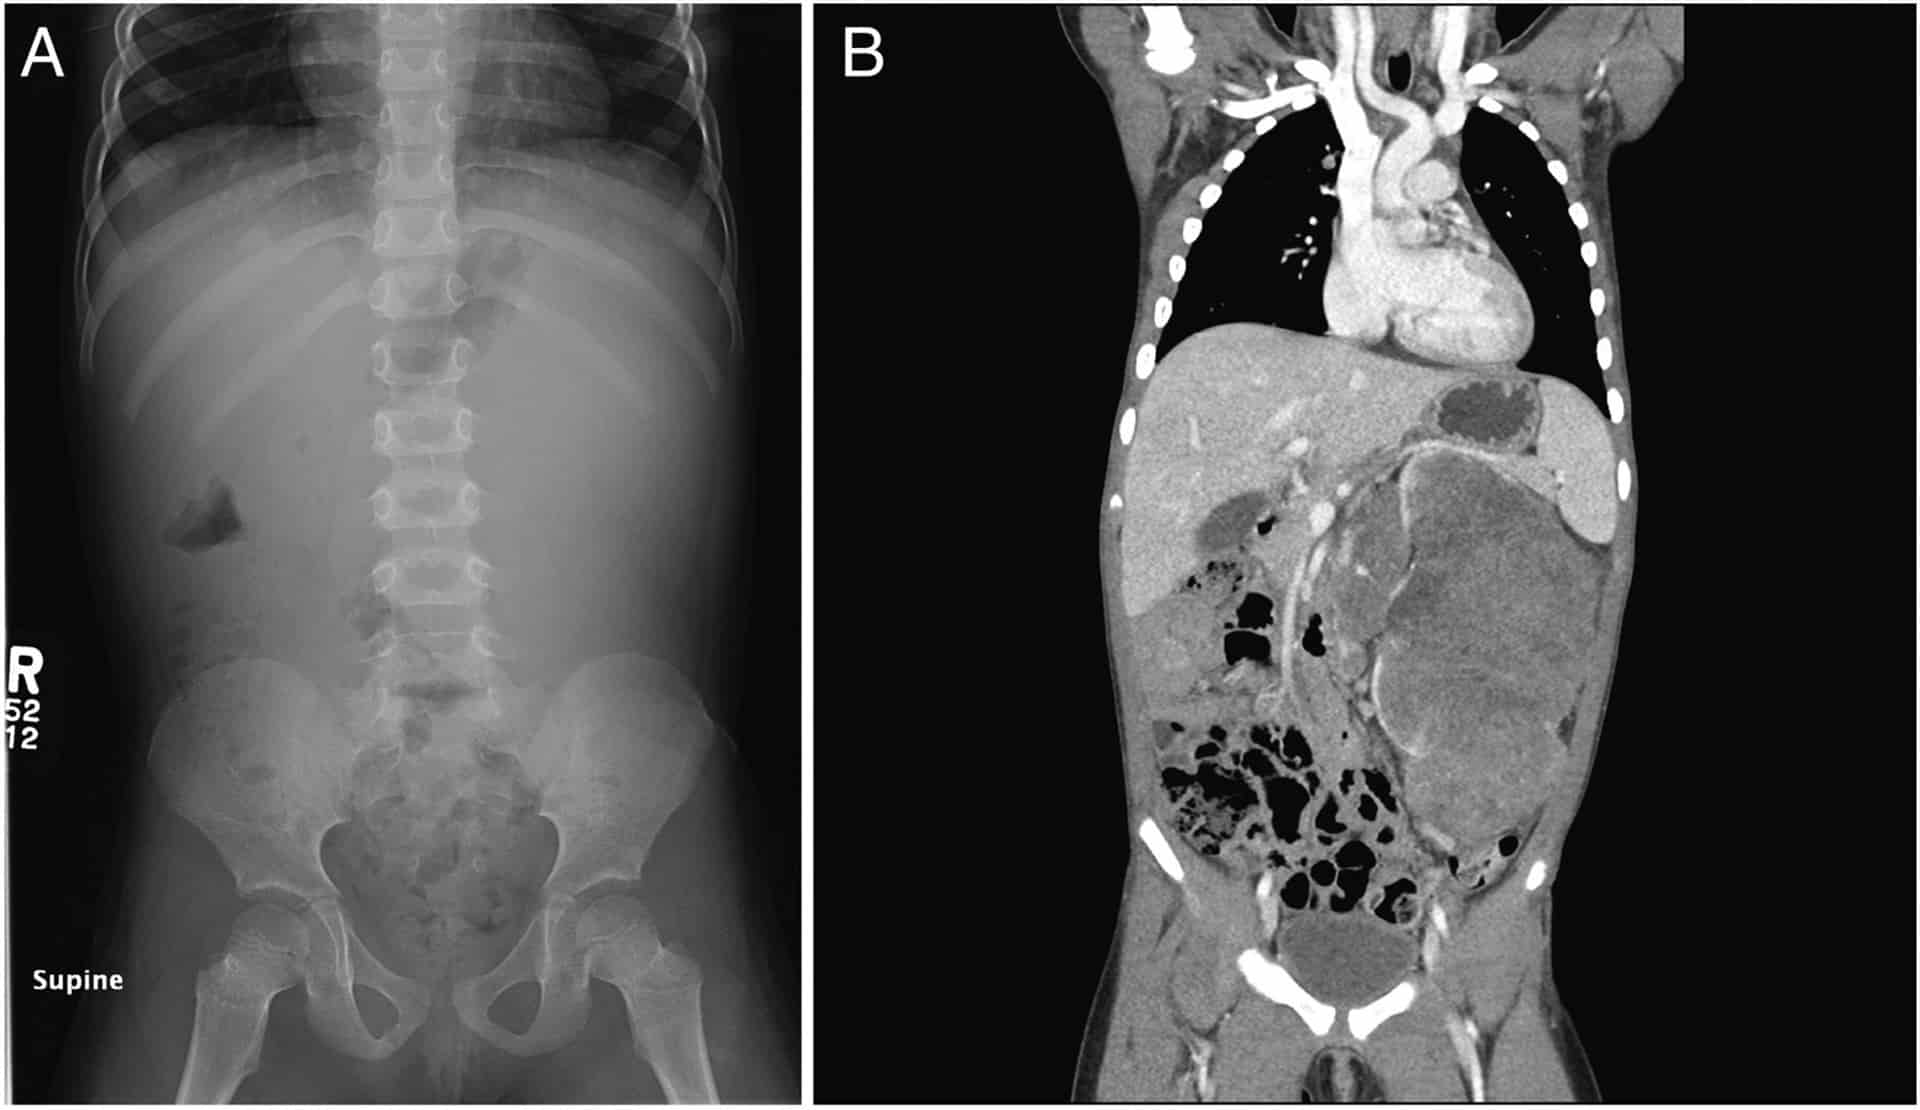

Por otra parte, el tumor se detecta por la presencia de un bulto durante una exploración de rutina. También se puede realizar una ecografía o una tomografía computarizada del abdomen para determinar la naturaleza y el tamaño del mismo.